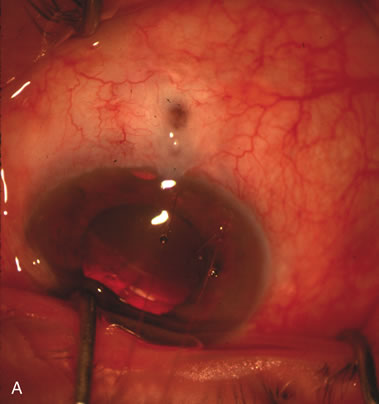

In years past, patients with both cataract and glaucoma frequently provided overwhelming surgical challenges for the ophthalmologist. The ability to carry out phacoemulsification through a 3.2-mm corneal incision along with inserting a foldable IOL is a vast improvement over 11-mm incisions that were common a decade ago (Fig. 1). The anatomical and inflammatory changes to the eye are less with small incision techniques, improving the likelihood of success with concomitant glaucoma surgery. Pharmacologic inhibition of fibrosis along with postoperative wound revision increases the long-term success rate of filtration surgery when combined with lens extraction. (Fig. 2). The learning curve may be steep at times, but the blending of cataract and glaucoma surgical skills slowly falls into place as the surgeon constantly learns and upgrades his or her technique.

Fig. 1. The anatomic advantage of small incision cataract surgery for the glaucoma patient. A. Long-term bleb function with a large cataract incision is difficult to achieve with either ECCE-trabeculectomy or trabeculectomy followed later by ECCE. This bleb failed to form sufficiently when combined with large incision ECCE. The inflammation, bleeding, and long-term wound healing with stimulation of fibroblasts associated with this technique are more likely to cause bleb failure. In addition, the increased iris manipulation necessary to deliver the nucleus and subsequent iris repair adds to the long-term breakdown of the blood aqueous barrier. B and C. Two-site phacotrabeculectomy has the advantage of small incision cataract surgery combined with separate site trabeculectomy. The incision size is one third the size of the standard ECCE. The inflammation is less severe, and cataract wound healing is confined to the temporal area. Visual rehabilitation with phacoemulsification and foldable IOL is much faster. Phacoemulsification allows successful lens extraction even in the unfriendly environment of a smaller pupil compared with ECCE. The trabeculectomy is performed in an entirely different site, well away from the wound healing associated with temporal phacoemulsification. The likelihood of this filter functioning long-term is greater than with ECCE-trabeculectomy. D. The surgeon also has the option of single-site phacotrabeculectomy with foldable IOL. Both the lens extraction and trabeculectomy are performed through one small 3.5-mm limbal incision.